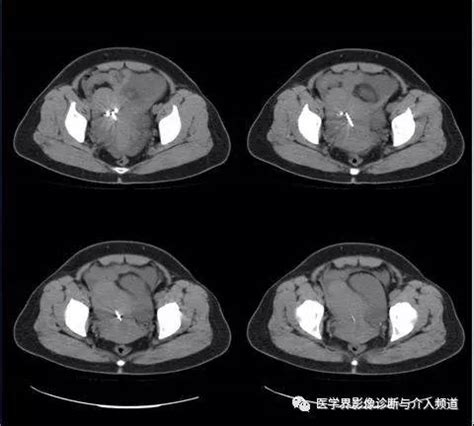

B超能不能检查出膀胱癌

膀胱镜检查是最可靠的诊断方法,通过膀胱镜可直接观察到肿瘤的位置、大小和形态,同时可取活检做病理诊断,为制定治疗方案提供重要依据;静脉尿路造影有助于排除肾盂和输尿管同时合并肿瘤的存在;B超和CT检查对膀胱肿瘤的分期具有重要价值;尿脱落细胞检查多用于肉眼不能发现的肿瘤和监测术后复发。